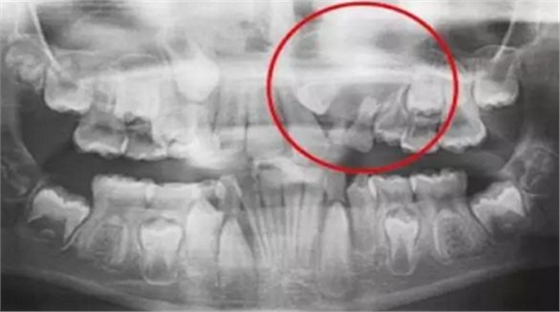

一名 23 區的9歲患者,在診所接受檢查時發現口內中存在大范圍含牙囊腫[圖1]。由于上頜竇下沿出現大范圍突出,迫切需要接受囊腫去除手術[圖2和3]。

囊腫去除[圖2]

囊腫去除后的大量骨缺損[圖3]